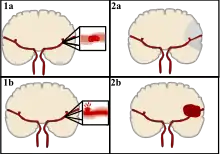

Classification

There are two main categories of strokes. Ischemic (top), typically caused by a blood clot in an artery (1a) resulting in brain death to the affected area (2a). Hemorrhagic (bottom), caused by blood leaking into or around the brain from a ruptured blood vessel (1b) allowing blood to pool in the affected area (2b) thus increasing the pressure on the brain.

Strokes can be classified into two major categories: ischemic and hemorrhagic.[18] Ischemic strokes are caused by interruption of the blood supply to the brain, while hemorrhagic strokes result from the rupture of a blood vessel or an abnormal vascular structure. About 87% of strokes are ischemic, the rest being hemorrhagic. Bleeding can develop inside areas of ischemia, a condition known as "hemorrhagic transformation." It is unknown how many hemorrhagic strokes actually start as ischemic strokes.[2]